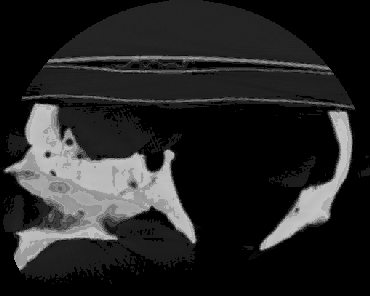

3D Human Skull

16bit greyscale CT image (reduced to 8bit gif)

This is layer 47 of 88 1.5mm sagittal scans of a human skull model w\ cap and mandibula.

Scanned with a PHILLIPS computer tomograph at

Institut für Klinische Radiologie at University of Muenster.